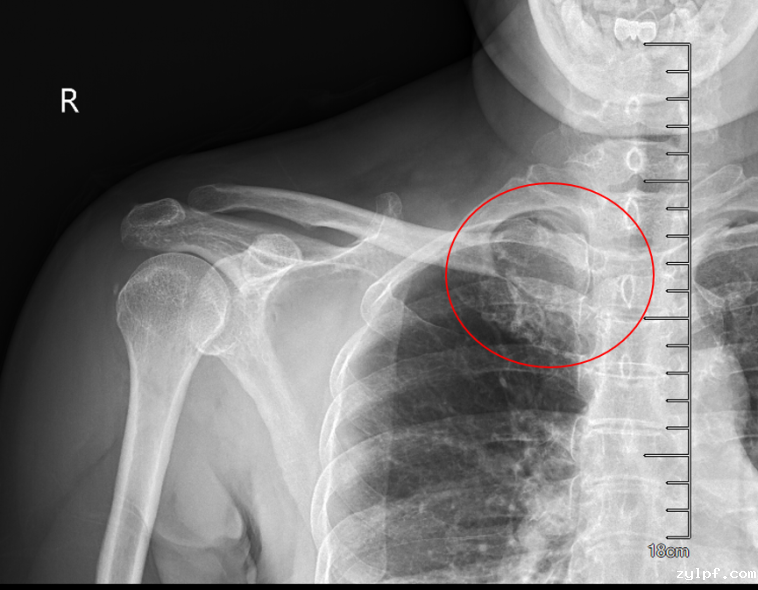

患者50岁女性,因体检发现右锁骨肿物10余天来诊。入院后X光片示右锁骨胸骨端膨大,密度减低,CT及MRI检查提示右侧锁骨局部骨性凸起伴周围肿块形成,考虑右锁骨胸骨端软骨肉瘤。

图片 1.png